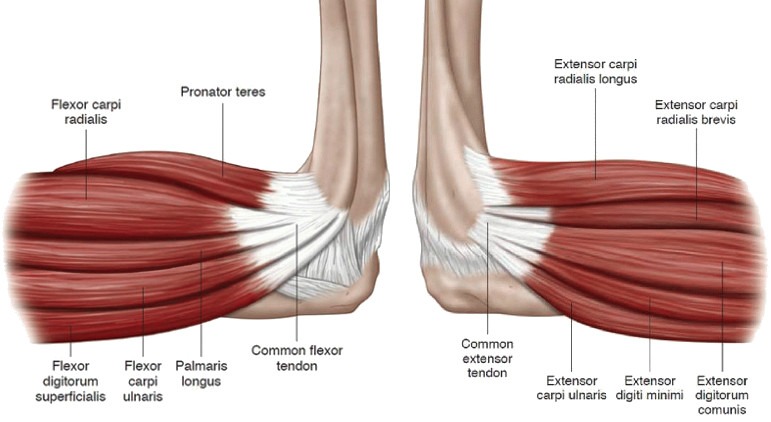

Анатомия мышцы Palmaris Longus